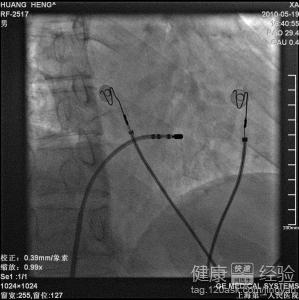

心髒射頻消融術後仍頻繁室性早搏怎麼辦

您好,之前的資料最好能夠提供。當時是何時做的手術,手術以後有沒有改善,手術後早搏有沒有消失過?是什麼時候復發的?有沒有其他器質性心髒疾病?這些都是很關鍵的問題。建議您近期復查心電圖、動態心電圖檢查再決定下一步治療方案,可以先使用藥物治療,必要時可以考慮再次射頻消融治療,當然建議到有經驗的中心進行,必要時可以考慮來我院周一下午心律失常門診就診治療。

1需要到醫院再次復查心電圖、動態心電圖等一些相關檢查結果,明確早搏復發的情況,比如早搏何時比較多,何時比較少,同時了解室性早搏的形態,初步判斷室性早搏的起源位置。

2在明確了室性早搏射頻消融前後的變化之後,可以進一步明確射頻消融的效果到底有沒有,同時對之後的治療方案(如如何調整有效的抗心律失常藥物治療,是否需要進一步行射頻消融治療等)的確定具有非常重要的意義。

3一般來說,早搏的治療需要考慮多方面因素。但可以先進行生活習慣調整(注意休息,避免刺激性食物藥物,如濃茶、咖啡等等),之後必要時用藥物治療(具體要看相關資料再行決定)。如果藥物治療後早搏仍比較多或者藥物治療無效,則建議必要時可考慮進行射頻消融治療。